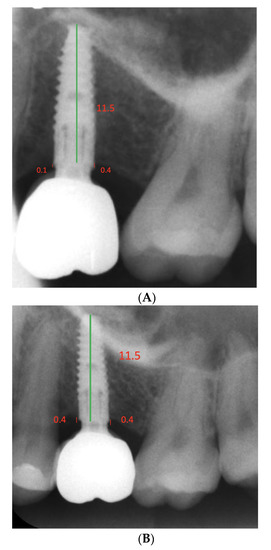

| Bone Levels | Baseline Mean (SD) | Follow-Up Mean (SD) | p-Value |

|---|---|---|---|

| Mesial | 0.45 (0.47) | 0.59 (0.42) | 0.30 |

| Distal | 0.57 (0.69) | 0.78 (0.59) | 0.17 |

| Maxilla (N = 11) | Mesial | 0.39 (0.31) | 0.65 (0.30) | 0.046 |

| Distal | 0.44 (0.29) | 0.78 (0.39) | 0.09 | |

| Mandible (N = 14) | Mesial | 0.5 (0.57) | 0.54 (0.50) | 0.87 |

| Distal | 0.68 (0.88) | 0.79 (0.73) | 0.65 |